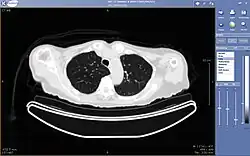

Teleradiology

Teleradiology is the ability to send radiographic images (x-rays, CT, MR, PET/CT, SPECT/CT, MG, US...) from one location to another.[58] For this process to be implemented, three essential components are required, an image sending station, a transmission network, and a receiving-image review station. The most typical implementation are two computers connected via the Internet. The computer at the receiving end will need to have a high-quality display screen that has been tested and cleared for clinical purposes. Sometimes the receiving computer will have a printer so that images can be printed for convenience.

Teleradiology is the most popular use for telemedicine and accounts for at least 50% of all telemedicine usage.